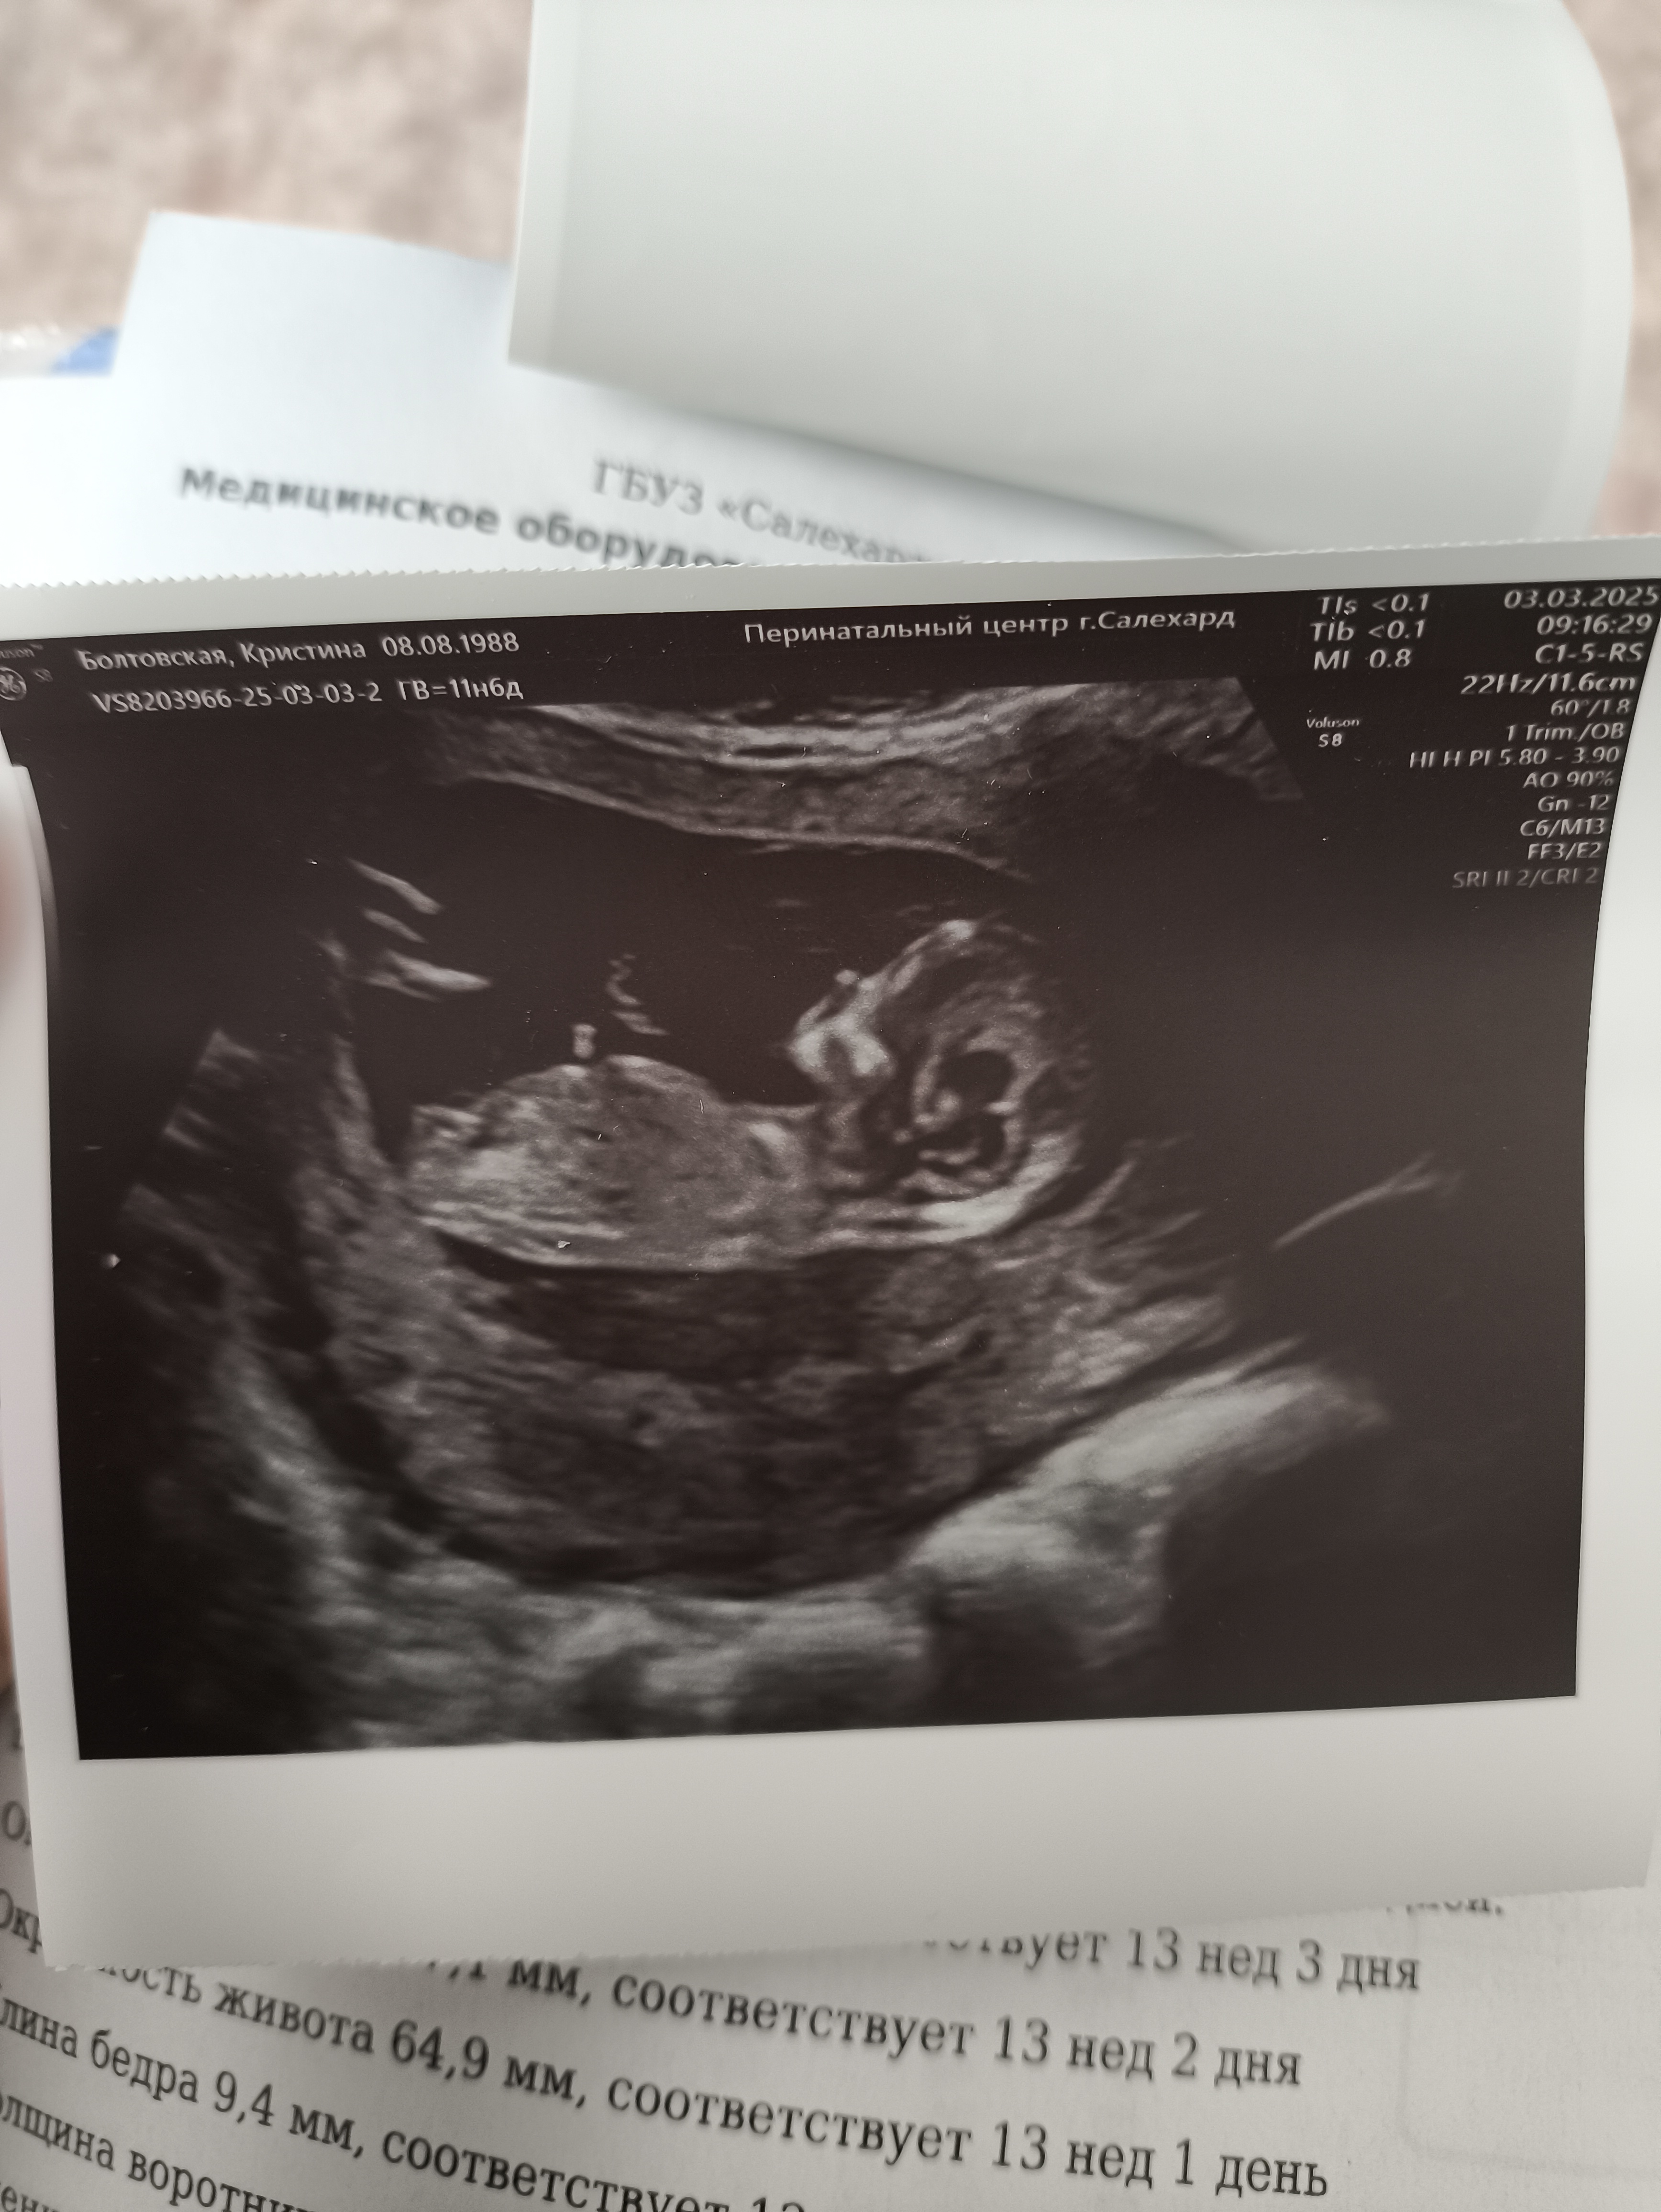

Первый скрининг. После ЭКО. Хорион частично перекрывает внутренний зев.

Хороший снимок,видно девочку. На таком сроке часто бывает,что перекрывает,смотрят на втором скриннинге.